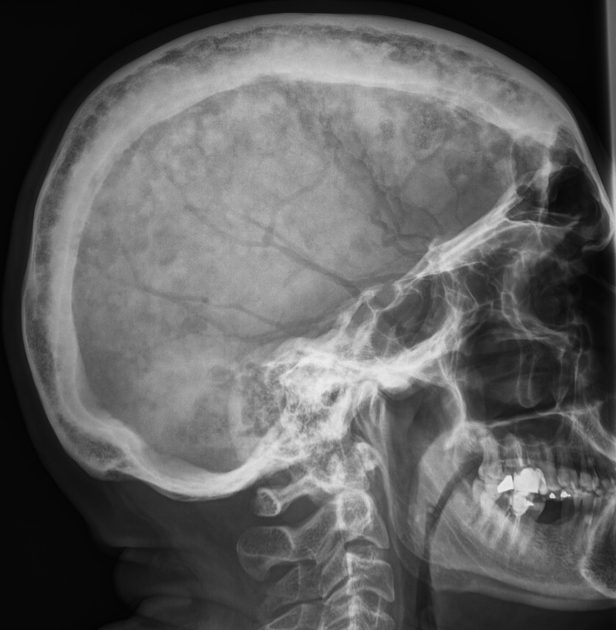

The following radiographs are most likely associated with which condition?

Explanation: ***Hyperparathyroidism*** - Classic radiological features include **subperiosteal bone resorption** (especially in phalanges), **salt-and-pepper skull** appearance, and **brown tumors**. - Additional findings may include **rugger jersey spine**, **loss of dental lamina dura**, and **osteoporosis** due to excessive **parathyroid hormone (PTH)** secretion. *Hyperpituitarism* - Radiographic changes primarily involve **enlarged sella turcica** and **acromegalic features** like enlarged hands, feet, and jaw. - Bone changes are typically **thickening and coarsening** rather than the resorptive patterns seen in hyperparathyroidism. *Hypoparathyroidism* - Characterized by **increased bone density** and **sclerotic changes** due to low PTH levels and calcium deposition. - May show **basal ganglia calcifications** and **cataracts**, but lacks the bone resorptive features typical of hyperparathyroidism. *Hyperthyroidism* - Radiological findings include **osteoporosis** and **accelerated bone turnover**, but without specific resorptive patterns. - May show **thyroid enlargement** on chest X-ray, but lacks the characteristic **subperiosteal resorption** seen in hyperparathyroidism.